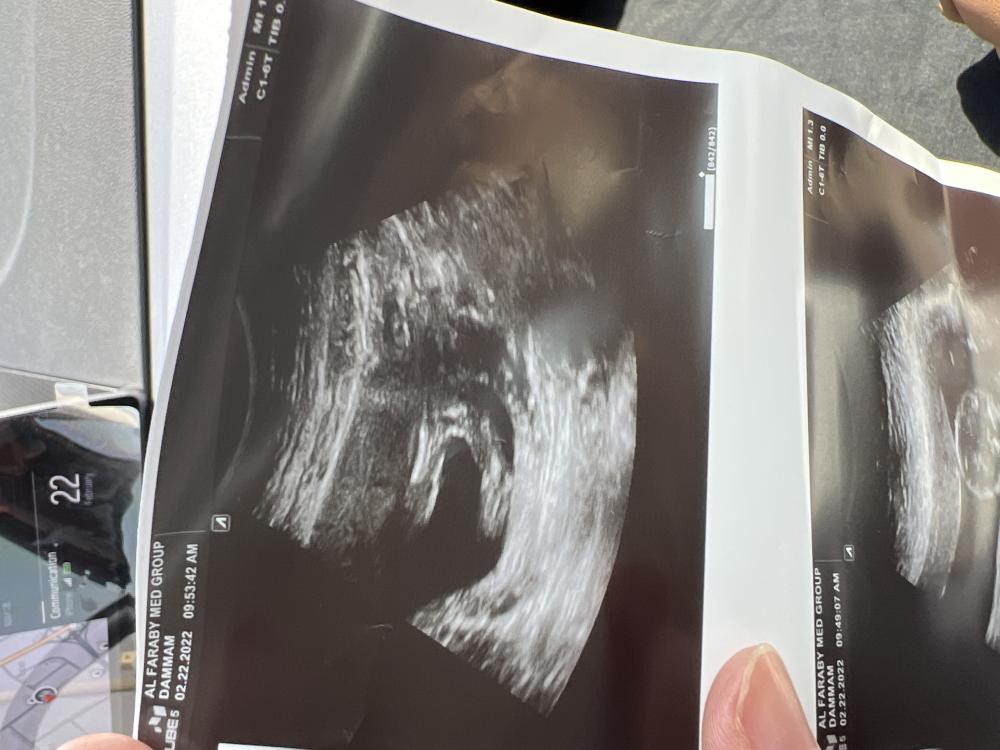

هاذي صورة السونار تقول ما اقدر اقول لان مو اكيد انتو ايش شايفين 🤣 بموت من اللقافه دفعت ٢٥٠ على هالسونار 😅

احس ولد بس بعده صغير العلم عن الله